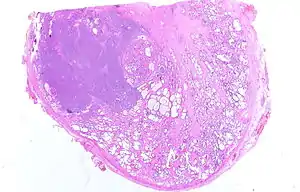

![]() Микрофотография инвазивной аденокарциномы простаты | |